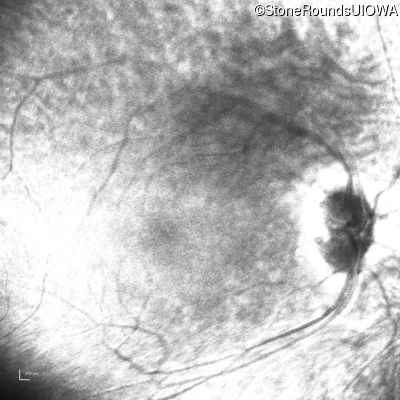

Infrared Fundus Photograph - Left - Light Perception

Exemplar